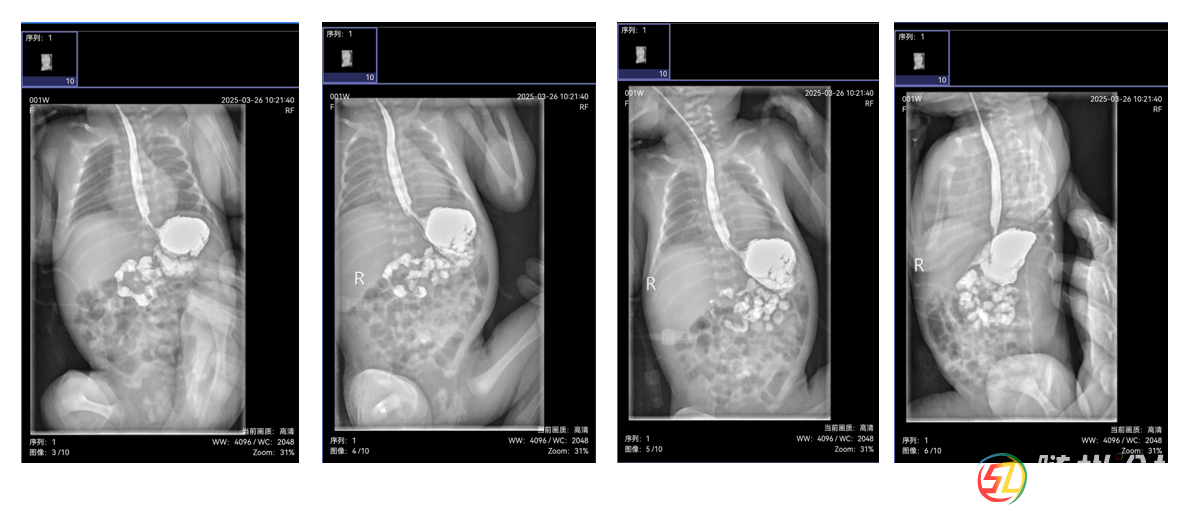

由于新生兒消化道畸形診斷技術(shù)要求高,隨州市中心醫(yī)院新生兒科副主任涂小瓊迅速啟動多學(xué)科協(xié)作機制,聯(lián)合本院超聲影像科副主任醫(yī)師涂朝霞行幽門管超聲檢查、醫(yī)學(xué)影像科副主任楊永剛行上消化道造影檢查,并積極聯(lián)系武漢兒童醫(yī)院新生兒內(nèi)科主任曾凌空教授、放射影像科主任彭雪華教授開展遠程會診。

會診中,彭雪華教授詳細解讀影像資料,明確診斷為“可復(fù)性胃翻轉(zhuǎn)”,排除了幽門肥厚;曾凌空教授結(jié)合患兒情況,制定了科學(xué)的喂養(yǎng)方案和后續(xù)治療計劃。此次會診不僅為朵朵的康復(fù)指明了方向,也為隨州市中心醫(yī)院積累了新生兒消化道畸形診斷的寶貴經(jīng)驗。